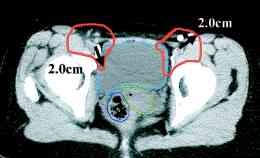

cervix ports, the node positions on CT scans (IJROBP

2002;54:1147) (A) Furthest

distance from lymph node to vessel wall. (B)

Para-aortic lymph node CTV. (C)

Common iliac lymph node CTV. (D)

External iliac CTV, including lateral group. (E) External

iliac CTV, including medial (obturator) group. (F)

Inguinal lymph node CTV. CTV depicted by thick orange line.

Small bowel demarcated by thin magenta, large bowel by thin

blue, rectum by thin dark purple, bladder by thin turquoise, and

uterus by thin yellow-green line. RTOG atlas